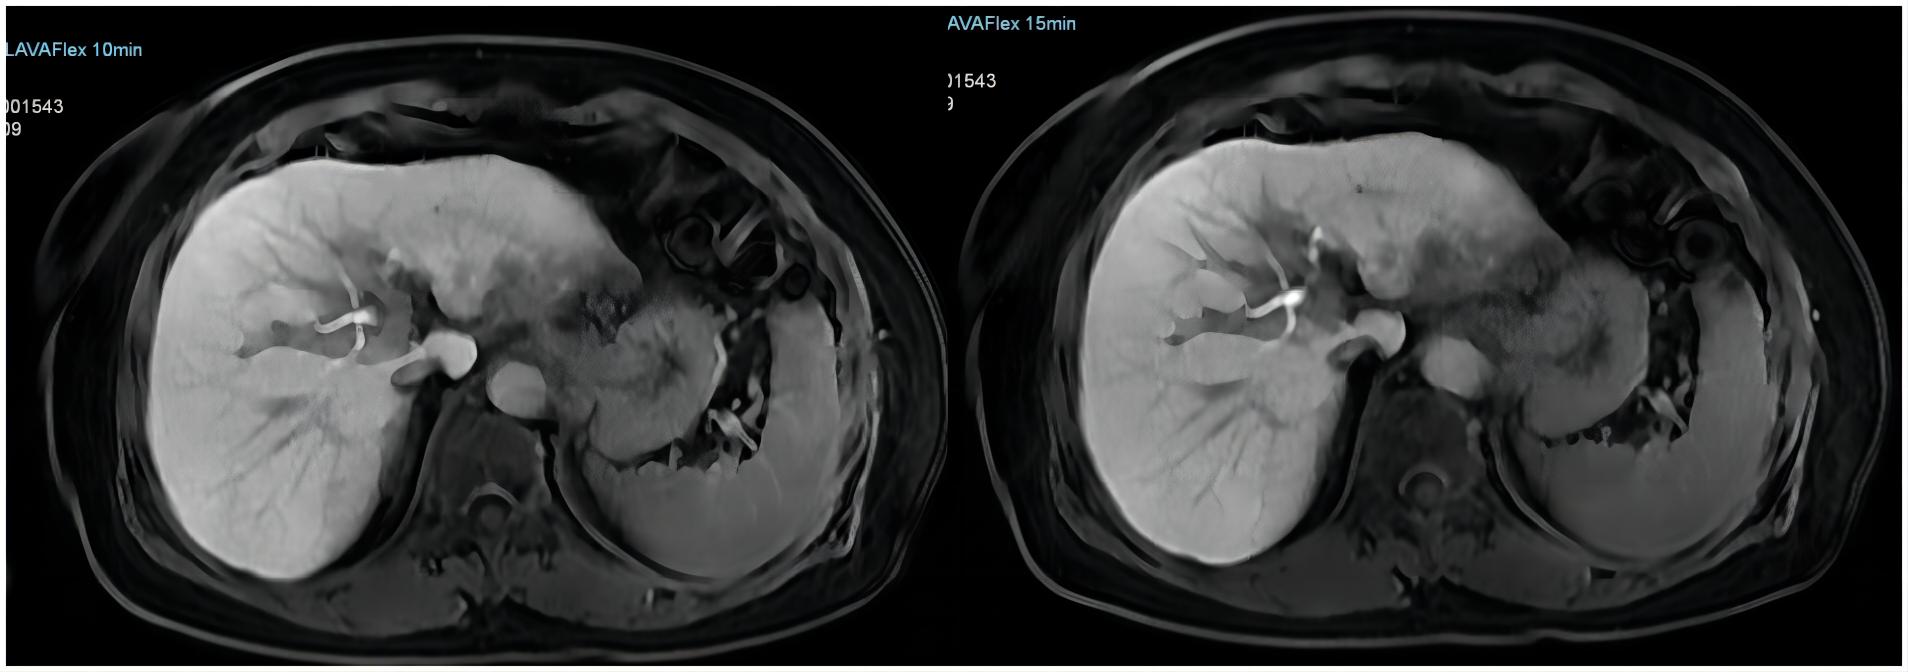

【技術四】肝特異性對比劑磁共振增強,普美顯(釓塞酸二鈉)注射液是一種肝細胞特異性對比劑,可以提供普通磁共振增強的圖像,還可以獲得清晰的肝細胞特異性圖像,肝特異性對比劑磁共振增強的優勢在于能發現小于1cm的肝內病灶,為肝癌提供特異性的診斷信息,提高肝內病灶的檢出率,有助于肝內病變的鑒別診斷。

【肝特異性對比劑磁共振增強(普美顯)】